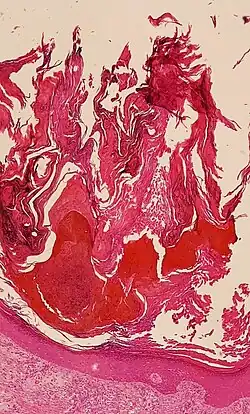

Histologic image of human epidermis in thick skin

The stratum corneum (Latin for 'horny layer') is the outermost layer of the epidermis of the skin. Consisting of dead tissue, it protects underlying tissue from infection, dehydration, chemicals, and mechanical stress. It is composed of 15 to 20 layers of flattened cells with no nuclei or cell organelles.

The human stratum corneum comprises several levels of flattened corneocytes that are divided into two layers: the stratum disjunctum and stratum compactum. The stratum disjunctum is the uppermost and loosest layer of skin. The skin's protective acid mantle and lipid barrier sit on top of the stratum disjunctum.[5] The stratum compactum is the comparatively deeper, more compacted and more cohesive part of the stratum corneum.[6] The corneocytes of the stratum disjunctum are larger, more rigid and more hydrophobic than those of the stratum compactum.[7]

The thickness of the stratum corneum varies throughout the body. In the palms of the hands and the soles of the feet (sometimes knees, elbows,[9] and knuckles) this layer is stabilized and built by the stratum lucidum (clear phase) which allows the cells to concentrate keratin and toughen them before they rise into a typically thicker, more cohesive stratum corneum. The mechanical stress of heavy structural strain causes this stratum lucidum phase in these regions which require additional protection in order to grasp objects, resist abrasion or impact, and avoid injury. In general, the stratum corneum contains 15 to 20 layers of corneocytes. The stratum corneum has a thickness of between 10 and 40 μm.